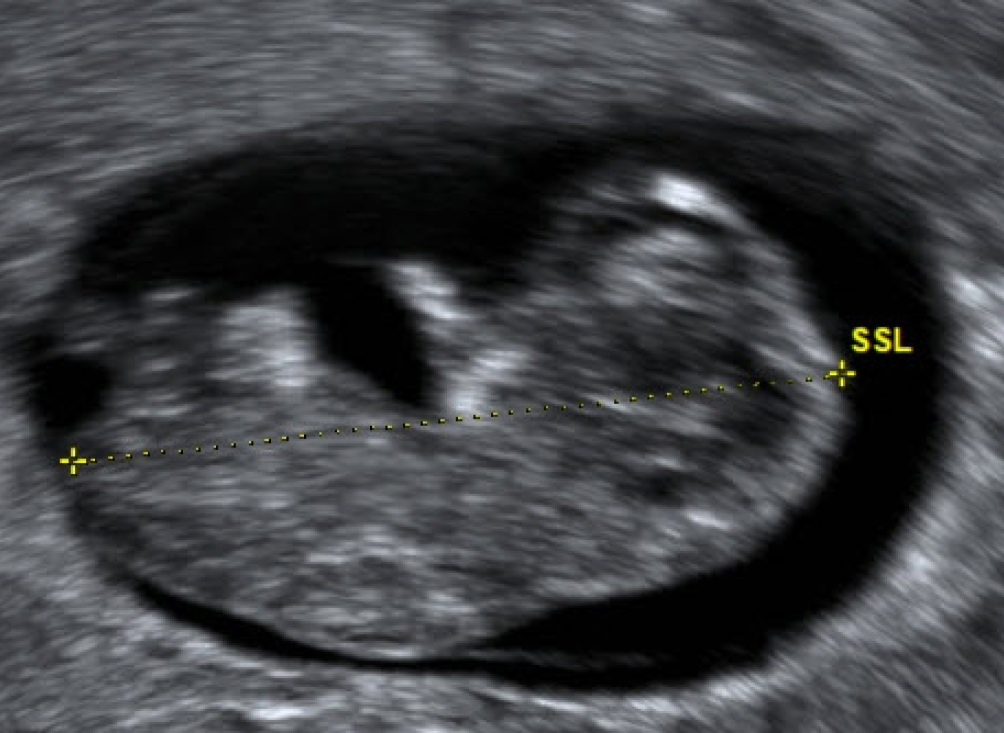

Ein 3‑D-Schall ist schön, die darin abgegriffenen Messstrecken sind allerdings wesentlich ungenauer als die von B‑Mode-Aufnahmen (Abb. 3 und 4).

Abb. 3

30 mm CRL – hier liegen Robinson, Pexsters und Hadlock alle bei 9 + 5 SSW

Bild vergrößern